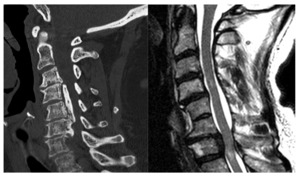

MRI remains the gold standard for evaluation of CM.4 MRI provides a high-fidelity, multiplanar reconstruction of the bony spine, neural elements, and soft tissue envelope of the cervical spine. Different anatomic structures can be evaluated in detail through various acquisition sequences and image post-processing. MRI images provide the best method for identifying which spinal levels are stenotic, what structures contribute to the stenosis, and the severity of stenosis and/or cord compression.9 The maladaptive formation of disc-osteophyte complexes in the anterior canal, buckling and hypertrophy of the ligamentum flavum, and facet hypertrophy posteriorly are the predominant sources of stenosis. MRI can also identify subtle changes within the spinal cord parenchyma, such as T1 hypointensity and corresponding T2 or Short Tau Inversion Recovery (STIR) signal hyperintensity. This may correlate with myelomalacia or spinal cord edema, both late findings of spinal cord compression, which may represent irreversible changes to the spinal cord. Lastly, recent advances in MRI technology may be useful for prognostication. Diffusion tensor imaging (DTI) can evaluate the individual tracts within the cord parenchyma. As this technology develops, it may be able to differentiate patients who can be reasonably monitored versus those who would benefit from early surgical decompression. This is especially important, considering up to 61% percent of asymptomatic patients have signs of anterior cord compression.12 MRI is an invaluable tool in the diagnosis, prognosis, and surgical planning aspects of CM.

Computerized Tomography

CT is also uniquely suited to the evaluation of CM. When MRI is contraindicated, CT myelography is a useful option to identify and quantify severity, though it lacks the prognostic benefits of evaluating the cord parenchyma. CT scanning is also paramount for positively identifying ossification of the posterior longitudinal ligament (OPLL), a clinical entity wherein the PLL ossifies along the dorsal vertebral body, resulting in canal stenosis and resultant neck pain, stiffness and neurological symptoms in some. OPLL can cause stenosis at the disc level as well as retro-vertebral. If this entity is not recognized preoperatively, it can lead to serious intraoperative complications.11 CT is also useful in pre-surgical planning as it better assesses bony anatomy and planned instrumentation. [Figure 1]